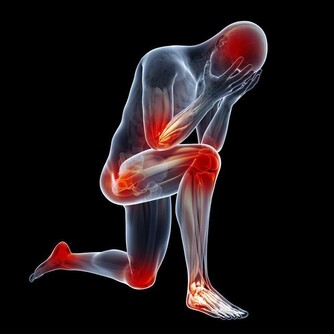

有一種口臭,跟口腔健康無關,而是身體其它部位發生問題而產生的氣味,通過口腔排出來而已。

不同氣味,暗示身體不同部位出問題。比如:

人體腎臟具有強大的代償功能,只要腎功能喪失不超過75%,仍能保持人體內環境的穩定。

所以,慢性腎衰病人早期常無明顯臨床症狀,往往容易誤診、漏診,使腎衰病人失去最佳的治療時機。

食慾減退和晨起噁心、嘔吐等,是慢性腎衰常見的早期表現。

另外,一些慢性腎衰病人還有一些特殊的臨床表現,如口腔內有氨的氣味,也就是你說的尿味,尿毒症病人更為明顯。